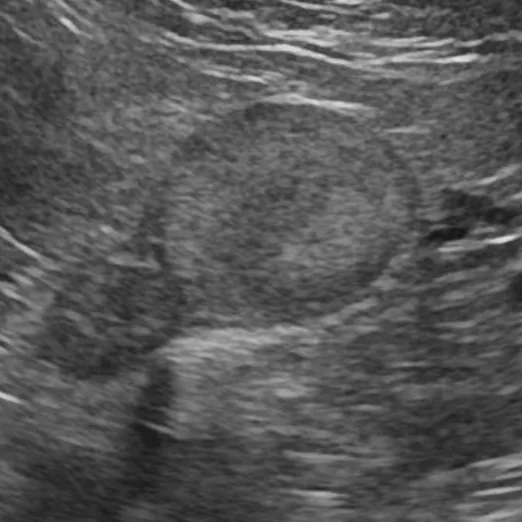

腹部超音波検査

副腎の評価(サイズや形)、血管との関連性を行います。